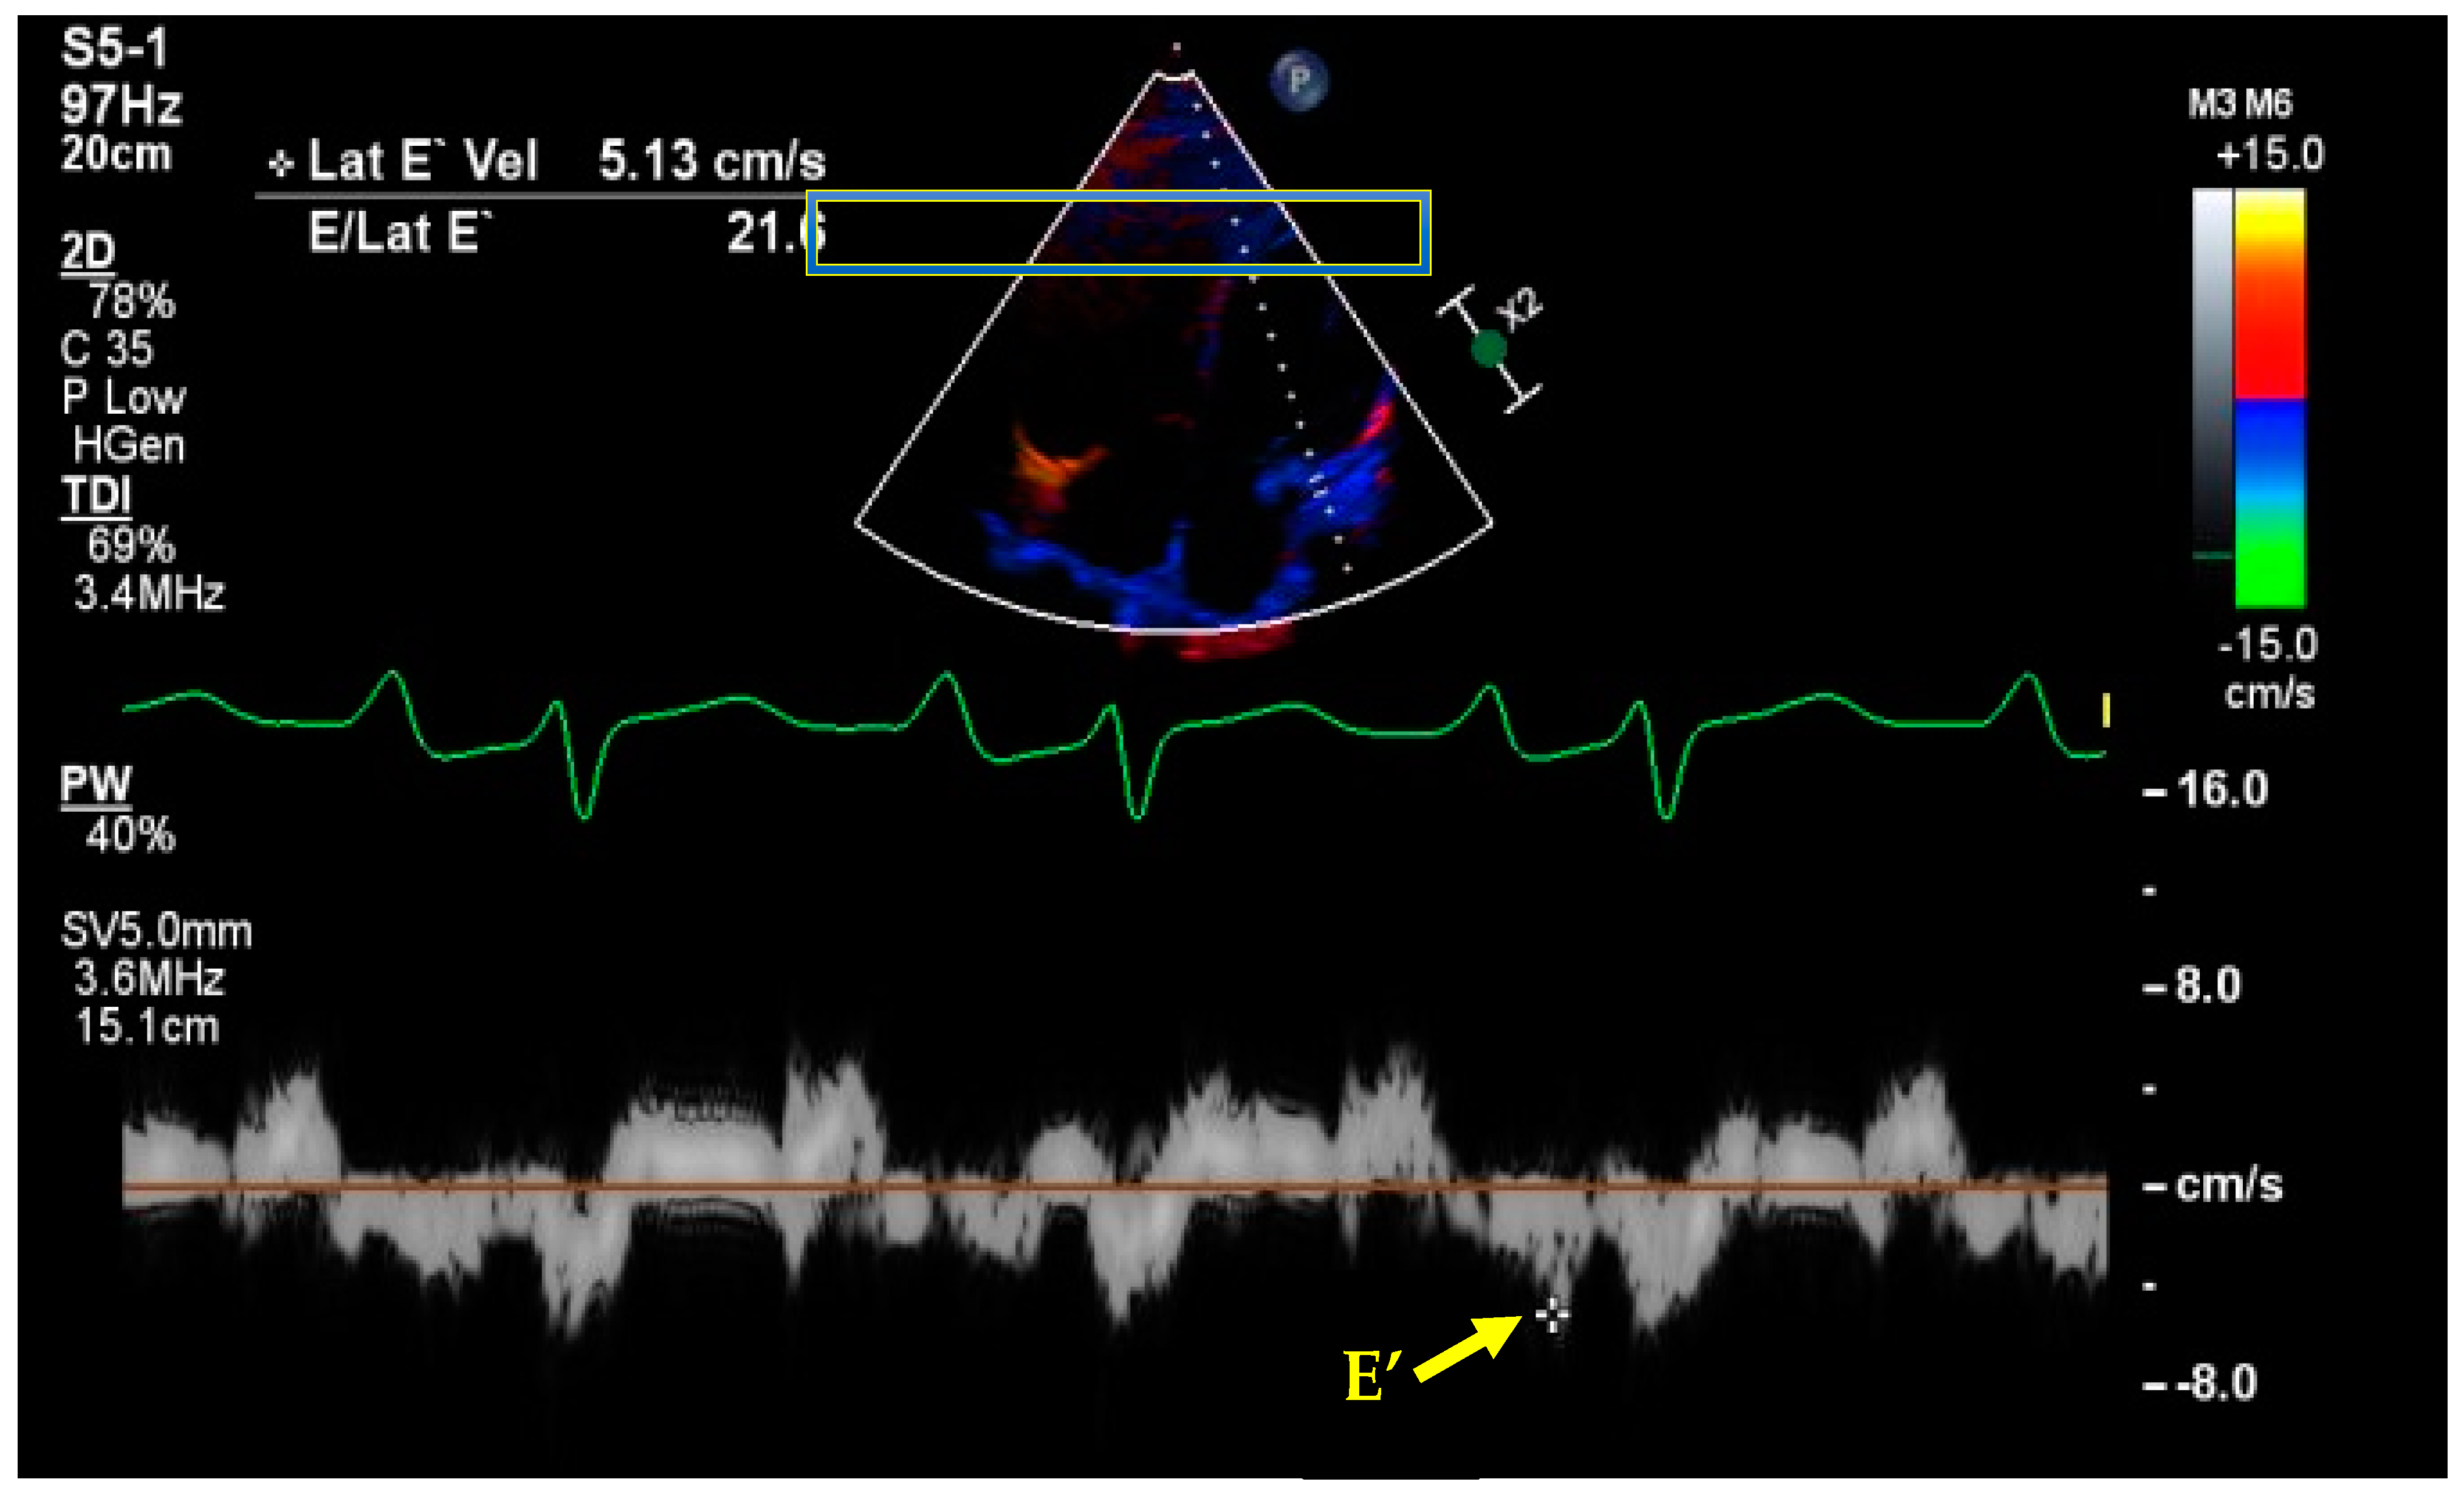

- Kim, J.S.; Yang, J.W.; Yoo, J.S.; Choi, S.O.; Han, B.G. Association between E/e ratio and fluid overload in patients with predialysis chronic kidney disease. PLoS ONE 2017, 12, e0184764. [Google Scholar] [CrossRef] [PubMed]

- Nagueh, S.F.; Middleton, K.J.; Kopelen, H.A.; Zoghbi, W.A.; Quinones, M.A. Doppler tissue imaging: A noninvasive technique for evaluation of left ventricular relaxation and estimation of filling pressures. J. Am. Coll. Cardiol. 1997, 30, 1527–1533. [Google Scholar] [CrossRef]

- Nagueh, S.F.; Smiseth, O.A.; Appleton, C.P.; Byrd, B.F., 3rd; Dokainish, H.; Edvardsen, T.; Flachskampf, F.A.; Gillebert, T.C.; Klein, A.L.; Lancellotti, P.; et al. Recommendations for the Evaluation of Left Ventricular Diastolic Function by Echocardiography: An Update from the American Society of Echocardiography and the European Association of Cardiovascular Imaging. J. Am. Soc. Echocardiogr. 2016, 29, 277–314. [Google Scholar] [CrossRef]